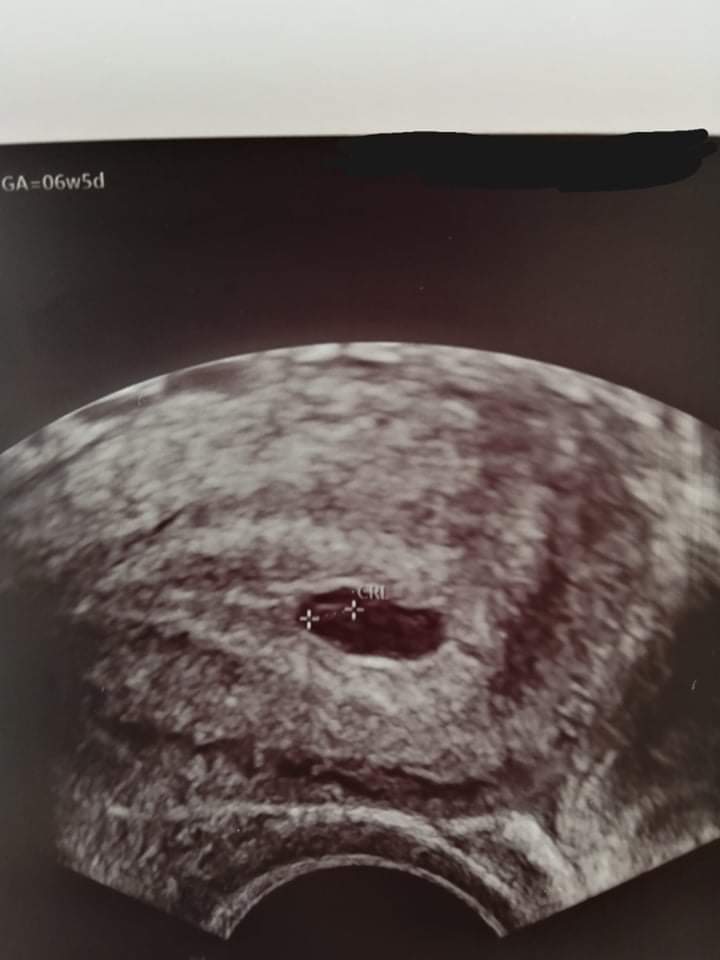

Odklejającą się Kosmówka

• received_2096097173870665.jpeg

Zaznaczone jest krzyżykami.

Co by nie było w ciągu dwóch tygodni to wszystko to jeden wielki rollercoaster.. czekam na kolejne USG, licząc się już chyba tylko z najgorszym bo przy tak słabych przyrostach HCG nie może być dobrze ale dalej wierzę w cuda...

Wiesz co, nie chce też wchodzić w kompetencje lekarza,ale ja bym obstawiała,że to zarys pęcherzyka żółtkowego a na pewno nie zarodek. Fizycznie jest to po prostu niemożliwe.